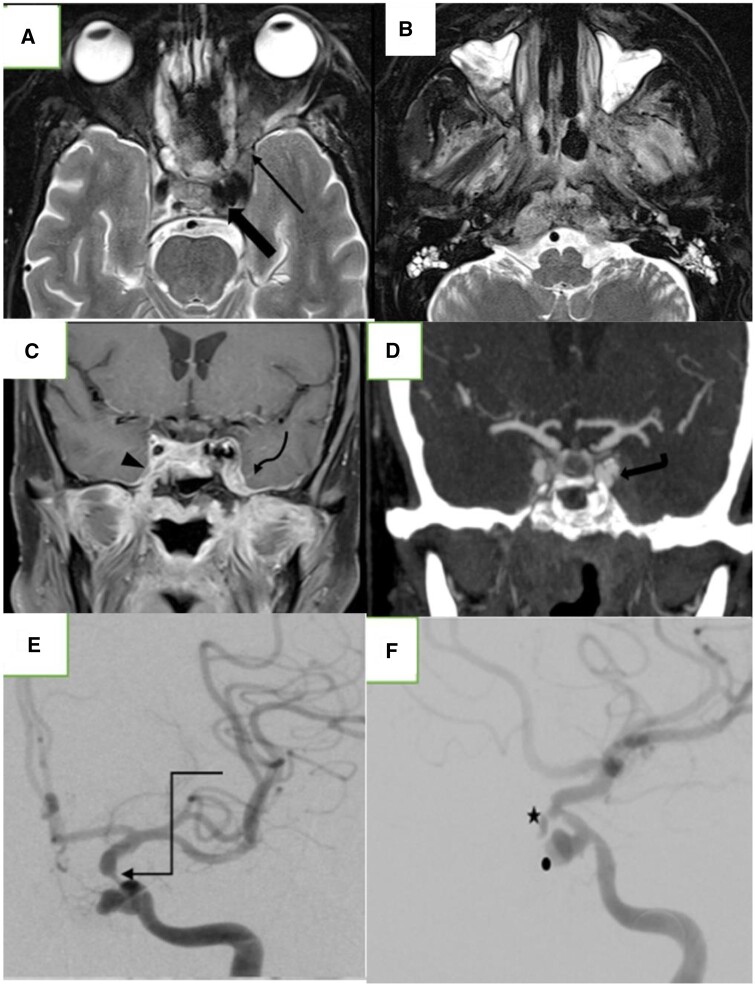

The coronavirus pandemic is now a public health emergency and has spread to nearly 206 countries across the globe. This novel disease has shaken the psycho-social, economic, and medical infrastructure of India. This has become even more challenging, considering the country's huge population. With the increase in the number of coronavirus disease (COVID) cases, our country has seen an unforeseen, unprecedented rise in a potential life and organ-threatening disease-mucormycosis. Mucormycosis is a deadly, extremely morbid, possibly life-threatening, and most feared complication of the coronavirus, caused by environmental molds belonging to the order Mucorales. Here, we report 2 cases of massive epistaxis due to internal carotid artery (ICA) pseudoaneurysm secondary to mucormycosis, post-COVID-19 pneumonia, which was managed by the endovascular route. To the best of our knowledge, there is very sparse literature available describing endovascular treatment of intracranial ICA pseudoaneurysm in a patient with COVID-induced mucormycosis.